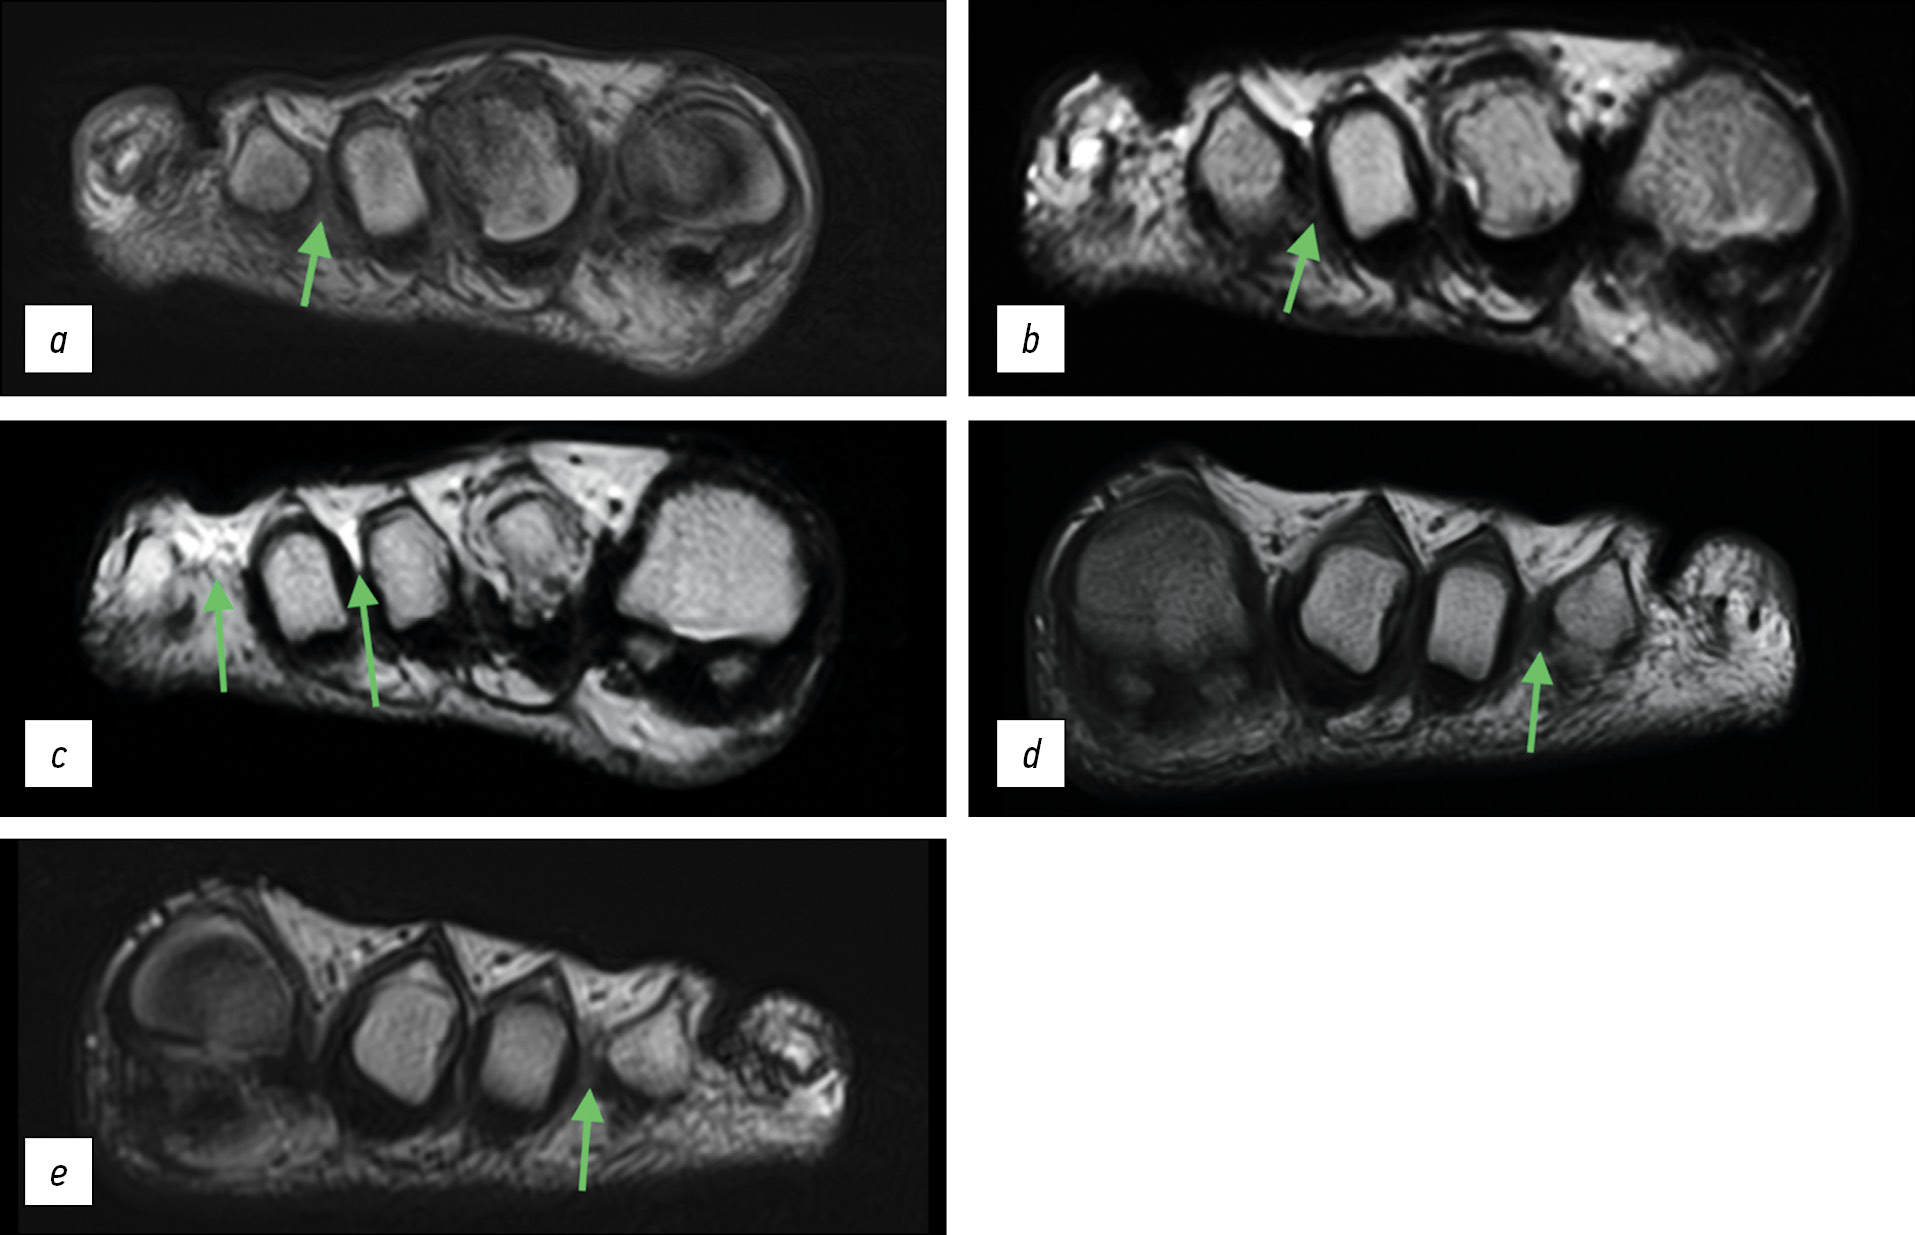

Пациентка Г., 30 лет. Периодические боли в переднем отделе обеих стоп беспокоят около полугода. За последний месяц отметила значительное ухудшение — дистанция безболевой ходьбы не более 50 метров. На данный момент пациентка проходит курс консервативного лечения препаратом габапентин в дозировке 300 мг со слабым положительным эффектом. На протяжении всего текущего периода обострения пациентка нетрудоспособна. Ранее была консультирована в сторонней клинике, выполнено УЗИ, выявлены признаки двусторонней невромы Мортона. Обратилась к нам в клинику для получения второго мнения с уже выполненным в сторонней клинике МРТ-исследованием на аппарате с напряжённостью магнитного поля 3 тесла (Canon Vantage Titan 3Т). При этом толщина срезов на представленных МР-последовательностях составила 4 мм.

На представленном нам исследовании из сторонней клиники на томографе напряжённостью 3 тесла толщина срезов составляет 4 мм. При подобном исследовании неврома менее 5 мм будет практически не видна. Столь явную неврому на столь скудном количестве срезов (26–27) мы видим из-за её большого размера: 12 мм правая стопа (рис. 3a–c) и 9,5 мм — левая (рис. 3d–e). Кроме того, учитывая подострое начало заболевания, хорошо видны отёк подкожно-жировой клетчатки и сопутствующий бурсит (рис. 3c).

Рис. 3. Пациентка Г., магнитно-резонансная томография: a — гипоинтенсивный сигнал по сравнению с окружающими тканями при Т1-взвешенной последовательности, правая стопа; неврома третьего межпальцевого промежутка; b — гипоинтенсивный сигнал по сравнению с окружающими тканями при Т2-взвешенной последовательности, правая стопа; неврома третьего межпальцевого промежутка; c — участок гиперинтенсивного сигнала при Т2-взвешенной последовательности (бурсит), отёк подкожно-жировой клетчатки, срез, следующий за изображением b в проксимальном направлении, правая стопа; d — гипоинтенсивный сигнал по сравнению с окружающими тканями при Т1-взвешенной последовательности, левая стопа; неврома третьего межпальцевого промежутка; e — гипоинтенсивный сигнал по сравнению с окружающими тканями при Т2-взвешенной последовательности, левая стопа; неврома третьего межпальцевого промежутка

Fig. 3. Patient G., MRI imaging: a — hypointense signal compared to surrounding tissues with a T1-weighted sequence, right foot; neuroma of the third interdigital space; b — hypointense signal compared to surrounding tissues with a T2-weighted sequence, right foot; neuroma of the third interdigital space; c — area of hyperintense signal on T2-weighted sequence (bursitis), subcutaneous fat edema, slice following image b in the proximal direction, right foot; d — hypointense signal compared to surrounding tissues on T1-weighted sequence, left foot; neuroma of the third interdigital space; e — hypointense signal compared to surrounding tissues on T2-weighted sequence, left foot; neuroma of the third interdigital space